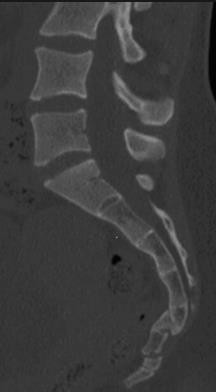

(5)薦椎骨折:圖七